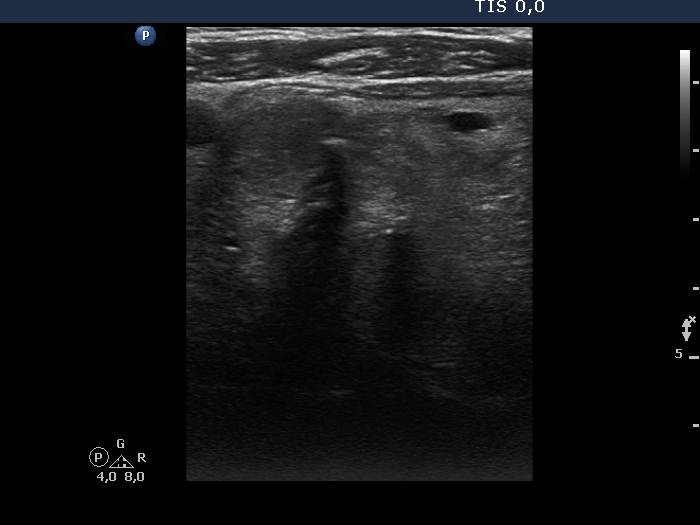

Ultrasonography. A large hypoechoic nodule occupied almost the entire right lobe. The lesion had both microcalcifications and coarse calcifications. The dimensions of the lobe were 58x55xminimum 80 mm, width, depth, length, respectively. The lower pole of the lobe did not come into sight while the patient swallowed. The nodule showed signs of perinodular blood flow. There was a hypoechoic nodule in the left lobe.